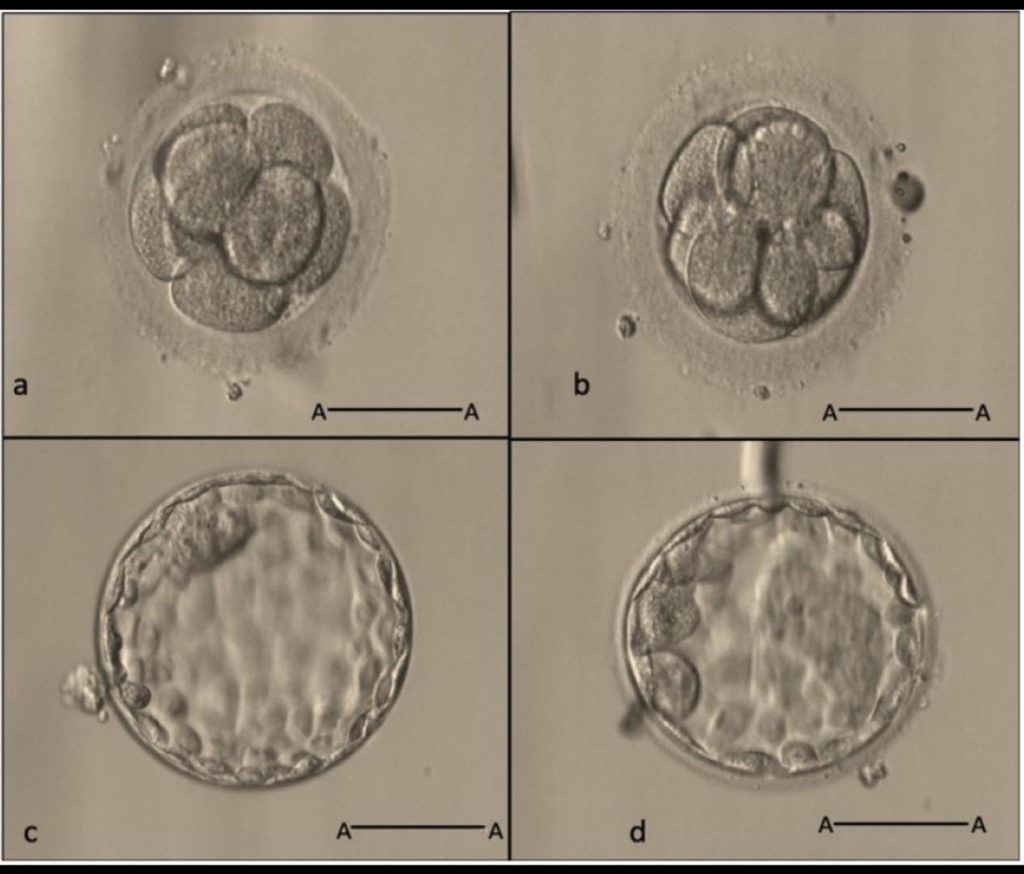

D3胚胎移植在卵子或受精卵數量不足情況下的主要優點,是能夠降低胚胎培養失敗導致無法移植的風險,

同時確保每個可用胚胎都獲得移植機會。多項研究顯示,在低胚胎產量的患者,

D3與D5移植每周期的持續妊娠率相近,但D3移植的移植取消率顯著較低。

與D5相比,D3移植可以減少因胚胎培養至D5未達到囊胚而無法移植的狀況,

特別是胚胎僅有1-2枚時,D5組取消率高達35%,而D3組僅約6%。

• 最大化可移植胚胎數

D3階段移植時常能移植較多胚胎(平均1.4顆),而D5通常僅有1顆可移植囊胚。